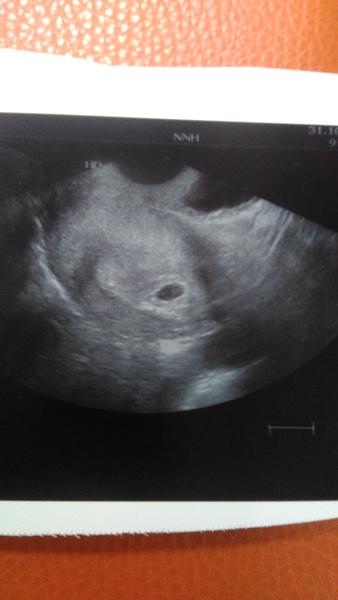

Ahojky, 3 dny mi meska menstruace, dnes jsem si dělala test hned,co jsem přišla z práce (cca v 5 odpo) a test jasně pozitivní. Bolí mě břicho trochu jako při menzes, bolí me prsa a věčný hlad. Přikládám fotku a prosím o názory zda je možné, aby to test ukázal takto brzy? Moc děkuji za rady postřehy 🙂